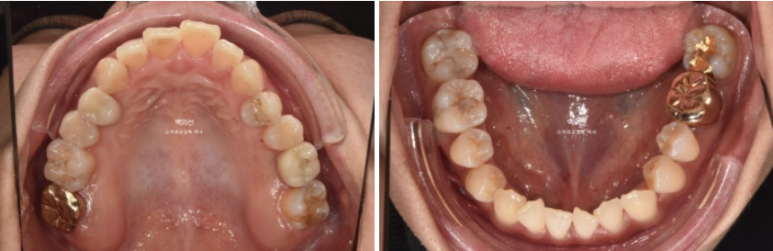

24.01~25.07

삐뚤 앞니는 가지런해졌습니다.

1년 반의 치료기간동안 치근흡수는 없고 치근평행도는 좋습니다.

특히 아래 치열이 뒤로 움직이면서 사랑니 공간이 많이 줄어든게 보입니다.